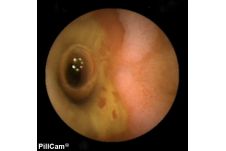

Der Dünndarm galt bis zur Einführung der sogenannten "Pillenkamera" als weitgehend uneinsehbarer Bereich. Dank einer innovativen Schluck-Kapsel mit Kamera und eigener Lichtquelle, die ohne eigenen Antrieb durch den Körper reist und währenddessen Bilder liefert, hat sich dies grundlegend geändert. Auch in der Klinik Mallersdorf wird diese Untersuchung durchgeführt, besonders zur Dünndarmdiagnostik.

Mit der Kapselendoskopie ist eine bildgebende Untersuchung des Dünndarms in einer für den Patienten schonender Weise möglich. Dabei wird eine Kapsel in Größe einer Penicillin-Kapsel geschluckt. Die integrierte Kamera nimmt während ihrer Reise durch den Magen-Darm-Trakt über einen Zeitraum von 8 Stunden Bilder auf und sendet sie an einen Rekorder. Die Kapsel wird dann auf natürlichem Wege ausgeschieden, die aufgezeichneten Bilder können mit einem speziellen Computerprogramm ausgewertet und befundet werden.

Die Kapselendoskopie wird besonders im Bereich des im Rahmen der Magen- und Darmspiegelung nicht einsehbaren Dünndarmbereichs verwendet. Sie hilft bei der Suche nach Blutungsquellen, chronisch entzündlichen Darmerkrankungen oder Tumoren.

Voraussetzung für eine Kapselendoskopie ist stets eine vorausgehende Magen- und Darmspiegelung. Sie ist also kein Ersatz, sondern eine Ergänzung für letztere.